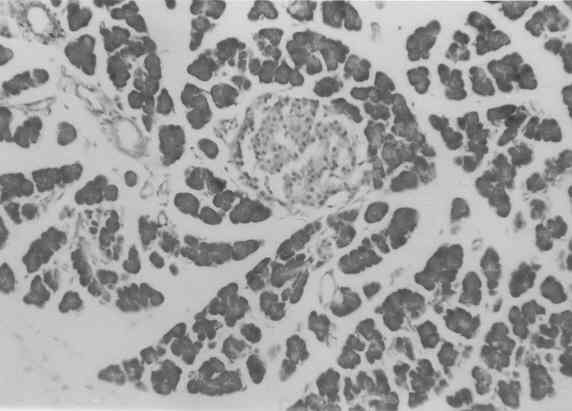

Figure 3 to 7 depicts the islet cells of the pancreas of rat in different groups. Fig 3 shows normal islet cells. The islets were shrunken in group 3 diabetic rat when compared with group1 control rat. Treatment of diabetic rat with the drug BDMCA in group 4 and glibenclamide in group 5 showed moderate expansion of islets.

Figure 3: Typical photomicrograph of the pancreas of control rat H and E x 10.

Figure 4: Typical photomicrograph of the pancreas of 15mg / kg b.wt of BDMCA treated control rat H and E x 10 shows normal islets.

Figure 5: Typical photomicrograph of the pancreas of STZ induced diabetic control rats H and E x 10 shows shrunken islets.

Figure 6: Typical photomicrograph of the pancreas of STZ induced diabetic rats treated with 15mg / kg b.wt of BDMC-A. H and E x 10 shows moderate expansion of islets.

Figure 7: Typical photomicrograph of the pancreas of STZ induced diabetic rats treated with 600 mg/kg b.wt of Glibenclamide. H and E x 10 shows moderate expansion of islets.